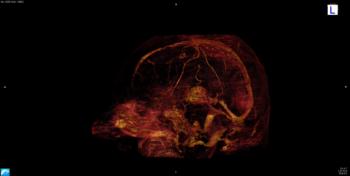

Dr. Gong and colleagues at Stanford have been studying deep learning as a way to achieve this goal. Deep learning is a sophisticated artificial intelligence technique that teaches computers by examples. Through use of models called convolutional neural networks, the computer can not only recognize images but also find subtle distinctions among the imaging data that a human observer might not be capable of discerning.

Video 1. Video shows volumetric visualization of algorithm-enhanced 10 percent contrast information.

Figure 3. Visualization of the deep learning model architecture that was used.